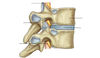

What are the three types of joints?

Fibrous

Cartilaginous

Synovial

Examples of Cartilaginous joints:

vertebrae, pubic symphysis

The 5 main characteristics of a synovial joint

1. Joint capsule

2. Ligaments

3. Joint cavity

4. Articular cartilage

5. Synovial membrane and fluid